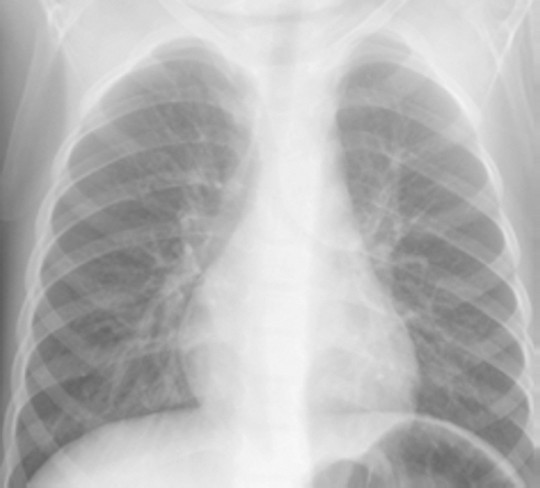

In children with solely viral pneumonia 49% had alveolar changes (p=0.001 compared with bacterial pneumonias, table 1). Antibiotics do not help viral pneumonia. Often pneumonia begins after a cold, with symptoms beginning after 2 or 3 days of a cold or sore throat.

Bacterial pneumonia may have a quick onset and the following symptoms may occur: Pneumonia is a serious lung infection usually caused by viruses or bacteria. The alveolar infiltrate was lobar in 36% of cases with bacterial pneumonia and in 15% of the those with viral pneumonia (p=0.001).